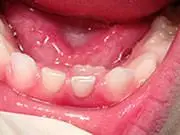

Baby Teeth - Pediatric Dentist in Ardmore, PA  Adult Teeth Coming in Behind Baby Teeth

This is a very common occurrence with children, usually the result of a lower, primary (baby) tooth not falling out when the permanent tooth is coming in.  In most cases if the child starts wiggling the baby tooth, it will usually fall out on its own within two months. If it doesn't, then contact your pediatric dentist, where they can easily remove the tooth.  The permanent tooth should then slide into the proper place.